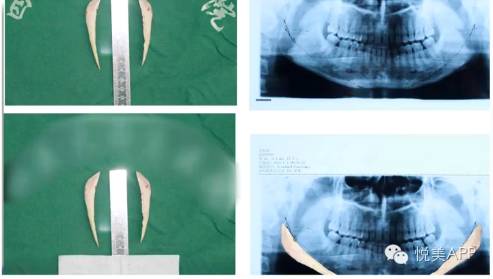

2、拍一张头颅的X光片——

来计算出下颌角的角度,与病人反复的沟通,了解患者的意愿。

3、拍一张头颅的定位、正侧位片

4、拍一张口腔的曲面断层全景片——能够一比一的复制出下颌角的下颌骨状况,还能看到神经管和神经孔,这个片子大家很熟悉啊,有时候治疗牙根也会拍。

5、在有条件的医院里,还会给换这叫进行三维CT,得到最准确的数据——